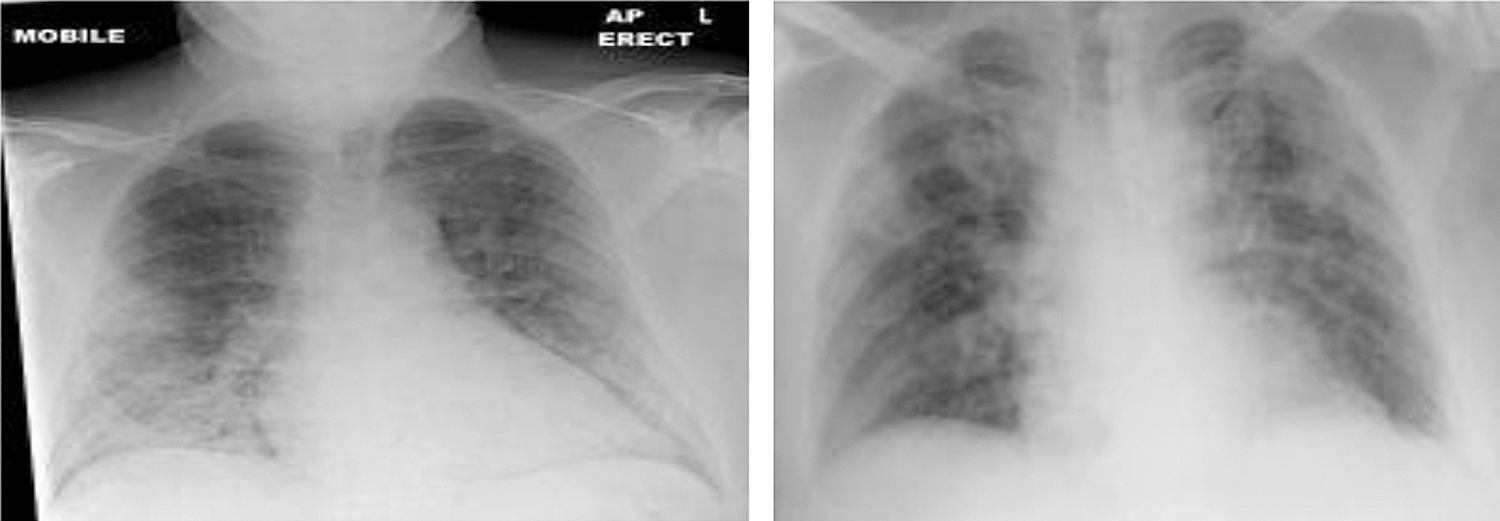

A total of 1000 X-ray images are collected from GitHub and shared by Cohen et al. [33]. There are four classes of images. Among the available images, 250 COVID-19 and 250 normal images are selected. The dataset also includes 250 Pneumonia Viruses and 250 Pneumonia Bacteria for a total of 1000 images. The dataset is balanced due to the fact that each class has 250 images. Fig. 3 shows a sample of the normal and healthy chest X-ray images, while Fig. 4 shows the images of the COVID-19 affected patients.

Figure 3: Chest images of normal and healthy people

Figure 4: Chest X-ray of COVID-19 affected people